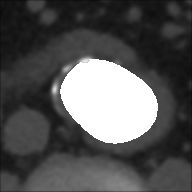

At this point, the dataset is ready for the processing in the portal ImageLab. The latter, takes as input the basal ROI and its corresponding CM one, together with their respective binary masks. These, are used by the algorithm to create the image (see Fig. 2), and consequently to detect the vessel. As depicted in Fig. 4, in output the extracted image is provided, along with a colored map where green highlights pixels correctly classified by the algorithm, red indicates misclassified ones, and white indicates the areas the algorithm should have identified but did not. Adjacent to this, similarity indices described before are presented, computed by considering the CM image as the target, which is provided as input for this purpose. We have processed in the portal each slice of our dataset.

| Patient | Basal | CM | Processed | DCI | TI | Em |

|---|---|---|---|---|---|---|

| P14 | 0.894 | 0.809 | 0.191 | |||

| P19 | 0.829 | 0.708 | 0.292 | |||

| P20 | 0.778 | 0.637 | 0.363 | |||

| P22 | 0.838 | 0.721 | 0.279 | |||

| P26 | 0.877 | 0.781 | 0.219 | |||

| P30 | 0.846 | 0.733 | 0.267 |